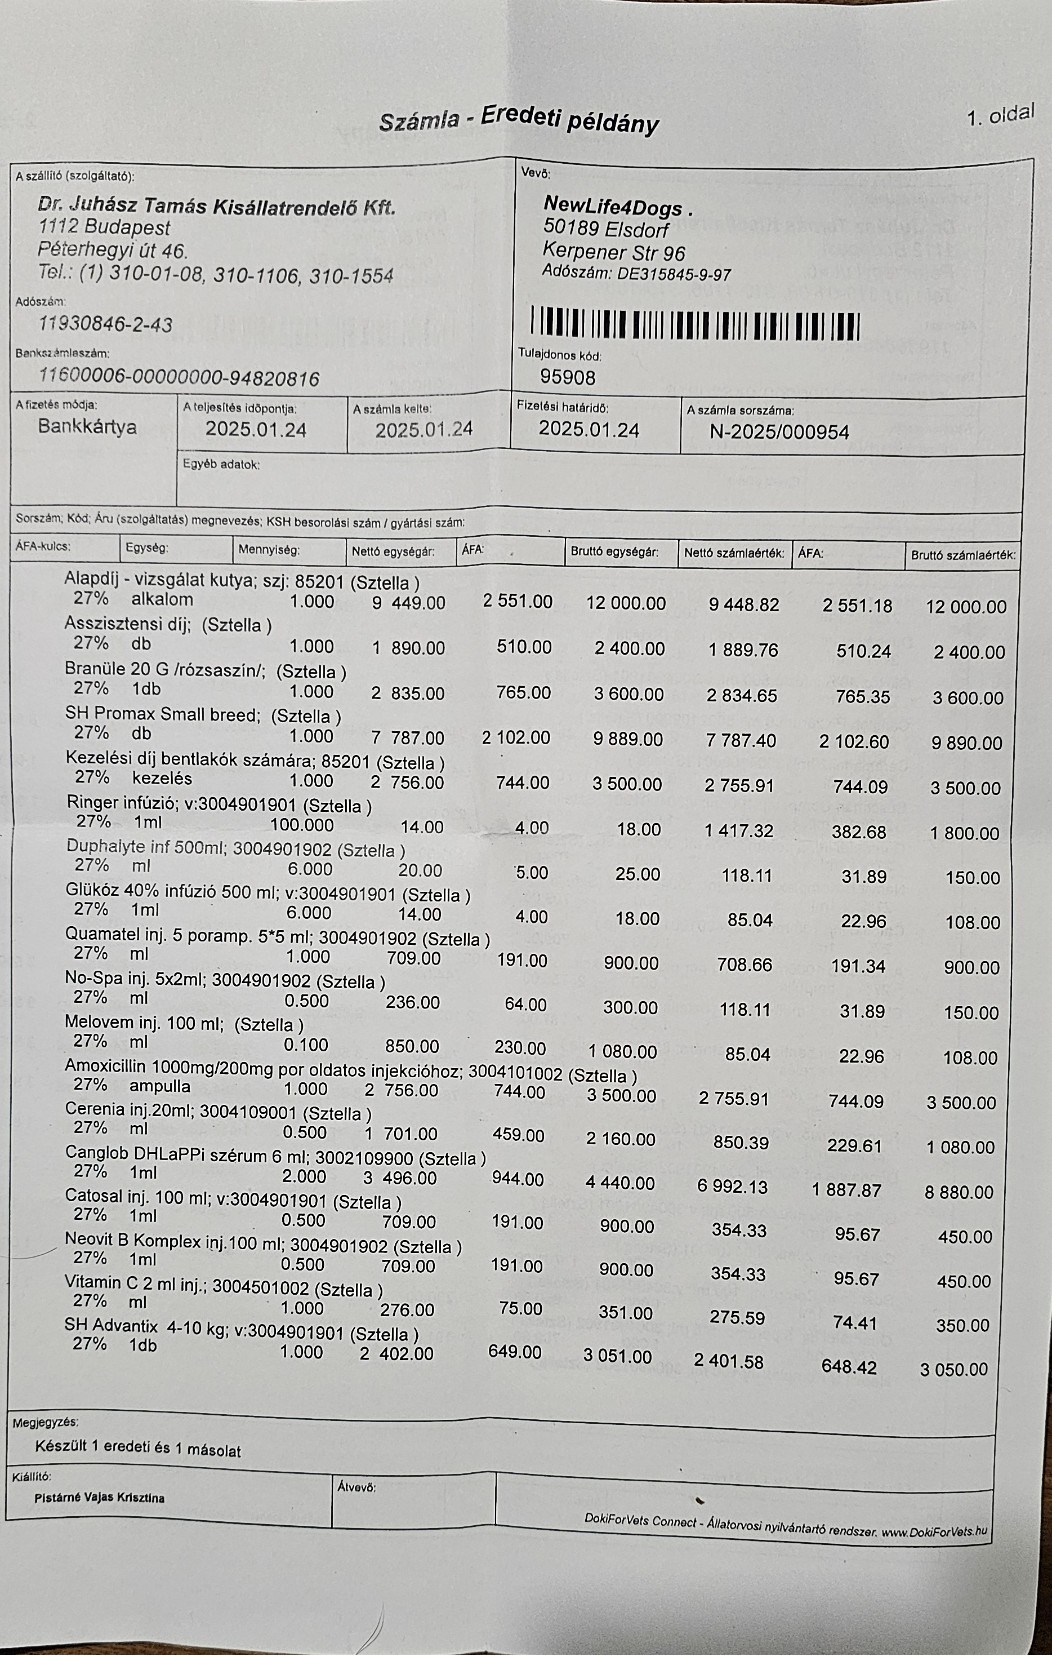

So zum Beispiel unsere kleine Stella, ein Welpen Mädchen das hier im Wald aufgefunden wurde. Nur 4 Tage nach Ankunft ging es Stella extrem schlecht und wir brachten sie in die Tierklinik zur stationären Aufnahme. Dort wurde sie intensivst medizinisch behandelt und musste 9 Tage in der Klinik verbleiben. Nur dieser eine Klinikaufenthalt verursachte Kosten in Höhe von 261.000,00 Forint ( ca. 640,00 Euro). Medikamente für die weitere Versorgung unserer Hunde musste bestellt werden. Ebenso Welpenfutter mussten wir nachkaufen. In den ersten Wochen wurden einige Hunde vergesellschaftet, damit die Quarantänestation wieder freie Zwinger hat. Denn in der Tötung warten Hunde darauf von uns abgeholt zu werden. Dies wird nun in den nächsten Tagen geschehen. Auch Klinikbesuche Kastrationen wurden wieder durchgeführt. Alleine hierfür betrug der finanzielle Aufwand ca. 750.000,00 (= ca. 1840,00 Euro) in der ersten Hälfte des Monats. Leider ist zur Zeit die Zeit extrem knapp, weswegen wir uns für die verspäteten Berichte entschuldigen. Doch die Rettungsaktionen und das Wohl unserer Schützlinge haben nun einmal Vorrang.

Nachdem die kleine Stella nach mehr als einer Woche die Klinik verlassen durfte, Mussten erneut einige unserer Neuzugänge dringende Not-OP´s und stationäre Aufnahme +ber sich ergehen lassen. So auch der kleine Sidney, den wir schwer verletzt mit gebrochenem Hinterbeinchen auf der Strasse in Nordungarn fanden. Sofortige Untersuchungen, Rüntgenaufnahmen und unverz+gliche Notoperation war erforderlich. Die Operation hat der kleine Mann gut überstanden. Nun benütigt er weitere Medikamente und Vitaminprodukte, damit er einen guten Heilungsprozess durchlaufen kann. Ebenso benütigt er 6 Wochen Zwingerruhe und Physiotherapie.